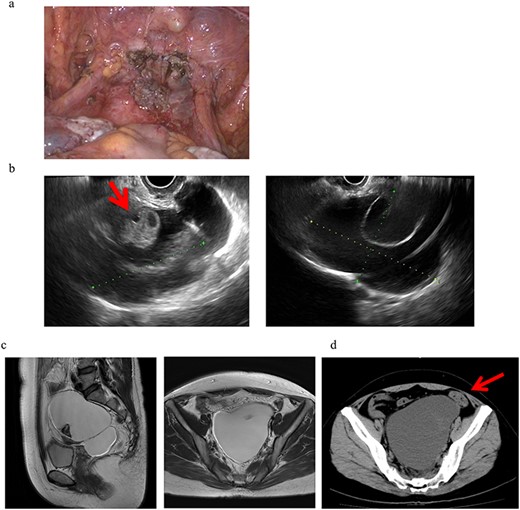

A 46-year-old woman, gravida 0 was diagnosed with uterine myoma. TLH was performed for symptom relief. As an intra-operative finding, strong adhesion was observed between the posterior wall of the uterus and the intestinal tract in the Douglas fossa, which led to difficulties detaching the adhesion. At the end of surgery, no abnormal findings, such as adhesions, were detected, as shown in Fig. 1a. The pathological diagnosis was uterine myoma with no evidence of endometriosis. Three months after surgery, a 13-cm cyst was detected on the vaginal stump by transvaginal ultrasound (US) in a post-operative follow-up (Fig. 1b). Pelvic magnetic resonance imaging (MRI) revealed PIC that was asymptomatic and, thus, no treatment was initiated (Fig. 1c).

Clinical findings of case 1. (a) Findings at the end of TLH. No abnormal findings were detected. (b) An US image of PIC in case 1. An ovary with a normal appearance was observed within the multilocular cyst. (c) T2-weighted MRI image. (d) CT findings with abdominal pain. A giant cyst appears to compress the sigmoid colon, resulting in abdominal pain and the impaired passage of the stool mass.

Eight months after surgery, the patient presented with lower abdominal pain and constipation. Computerized tomographic (CT) images showed a giant cyst compressing the sigmoid colon, resulting in abdominal pain and the impaired passage of the stool mass (Fig. 1d). To attenuate these symptoms, the cyst was punctured and ~700 ml of a dark brown smooth liquid was aspirated transvaginally, which attenuated her symptoms. The cyst subsequently increased in size to 12 cm but was asymptomatic and thus is being followed up without treatment.